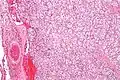

Micrograph of a carotid body tumor with the characteristic Zellballen. H&E stain.

The paragangliomas appear grossly as sharply circumscribed polypoid masses and they have a firm to rubbery consistency. They are highly vascular tumors and may have a deep red color.

On microscopic inspection, the tumor cells are readily recognized. Individual tumor cells are polygonal to oval and are arranged in distinctive cell balls, called Zellballen.[10] These cell balls are separated by fibrovascular stroma and surrounded by sustentacular cells.

By light microscopy, the differential diagnosis includes related neuroendocrine tumors, such as carcinoid tumor, neuroendocrine carcinoma, and medullary carcinoma of the thyroid.

With immunohistochemistry, the chief cells located in the cell balls are positive for chromogranin, synaptophysin, neuron specific enolase, serotonin, neurofilament and Neural cell adhesion molecule; they are S-100 protein negative. The sustentacular cells are S-100 positive and focally positive for glial fibrillary acidic protein. By histochemistry, the paraganglioma cells are argyrophilic, periodic acid Schiff negative, mucicarmine negative, and argentaffin negative.